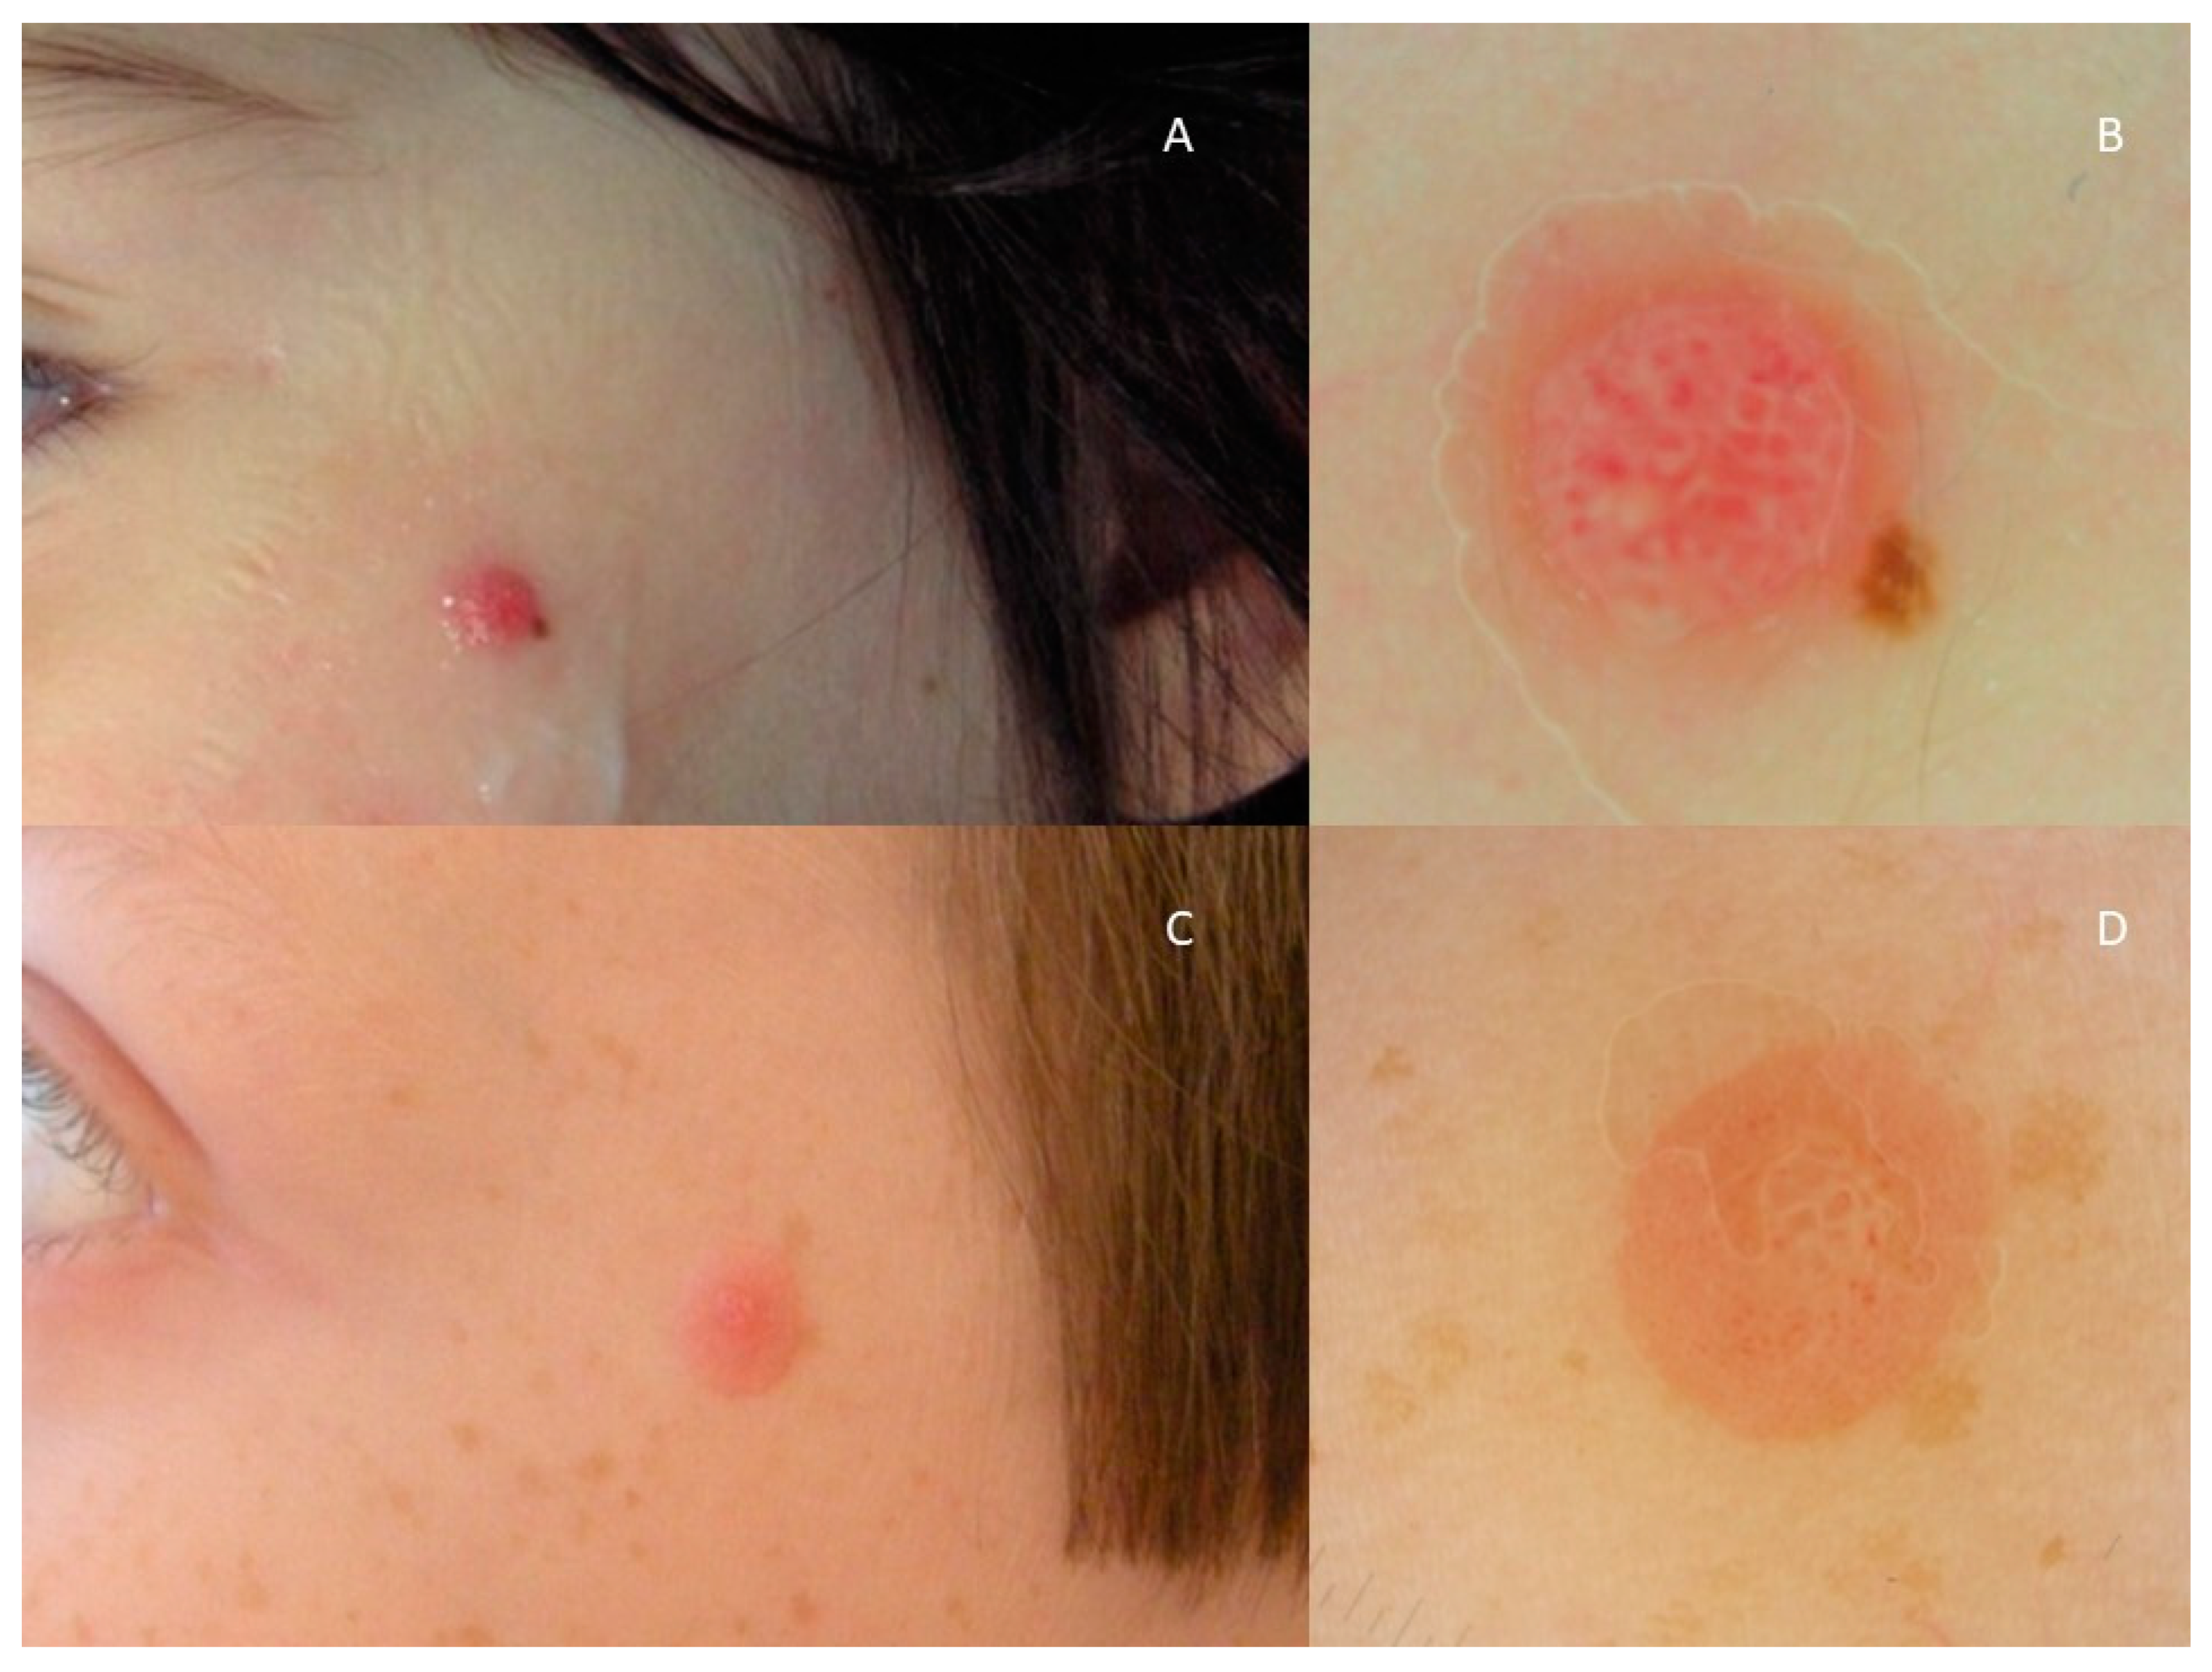

3. Results

4. Discussion